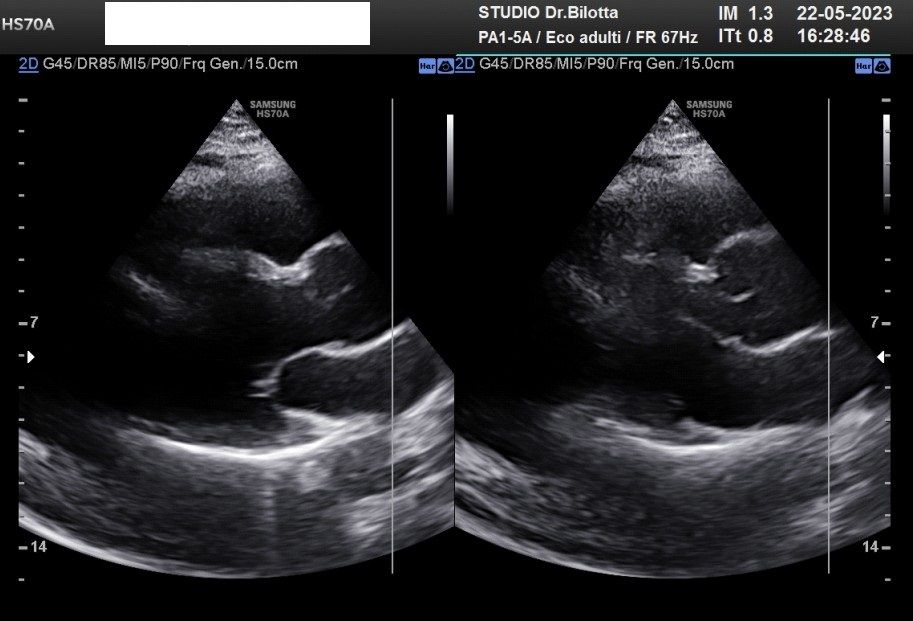

Foto e video